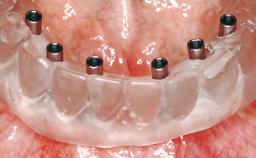

Immediate Loading of Eight Implants in the Maxilla and Six Implants in the Mandible and Final Restoration with Three-Unit and Four-Unit FDPs

Extensive scientific evidence has confirmed that immediately loaded implants with fixed full-arch provisional restorations can osseointegrate with success rates similar to conventionally or delayed loaded implants. A number of immediate-provisionalization techniques for edentulous jaws have been described. Some protocols differ when it comes to prefabricated provisional templates versus complete denture conversion; intrasurgical impressions versus direct relining; and cemented versus screw-retained provisional restorations. In this context, complete-denture conversion has been proposed for either intrasurgical impressions or direct relining. Another possibility is the utilization of a prefabricated provisional to be adapted either in the mouth (by direct relining) or in the laboratory (on a working model obtained from an intrasurgical impression).

Defining Characteristics Fully edentulous upper jaw to be rehabilitated with four or more implants

Modality 6+ implants with immediate loading